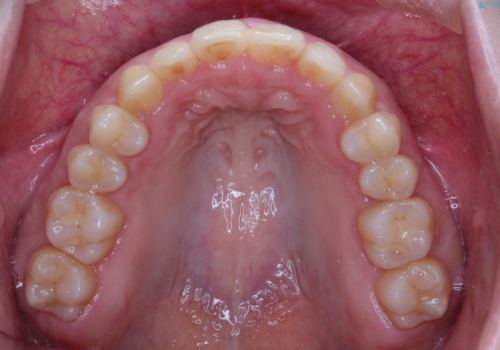

初診時の歯並びの状態としては、上下とも前歯部の中等度のがたつきがあり、その他に奥歯の噛み合わせのズレや、口元の突出感も認められました。

抜歯矯正の可能性もご提案しましたが、ご本人の強い希望もあり、抜歯なし/インビザラインによるマウスピース矯正にて治療を行いました。

本症例は、見た目、嚙み合わせ及び、治療期間や施術内容にご満足いただきました。